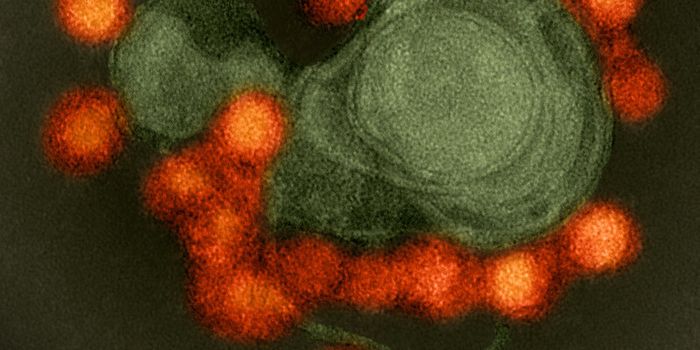

AUG 26, 2024Clinical & Molecular DXA colorized scanning electron micrograph depicts a Kupffer cell. / Credit: Thomas Deerinck, National Center for Microsco ...